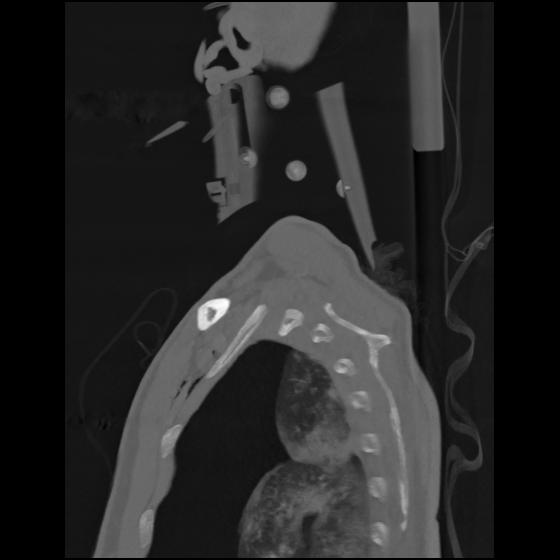

24 ANGIO,CE,Sag-MIP,5.000,ANGIO,Sag-MIP,